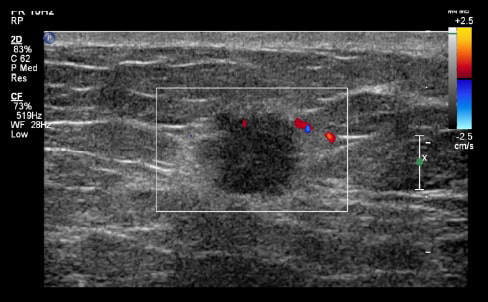

Case Example 3:

24-year-old female presents with a 2.7 cm palpable mass in her right breast. Ultrasound imaging demonstrates a solid mass with negative color doppler.

Case Example 3: Observations

The mass does not reveal any suspicious internal signal on the combined map with paired draping vessels anteriorly and a deoxygenated vessel posteriorly. Draping vessels are typical benign characteristics when seen in OA, as the mass pushes the vessels away versus penetrating or feeding the mass in a cancer OA image.

Balanced mixture of well-organized red and green vessels, small in size with large periphery vessels as seen in the OA Relative map.

- No biopsy - LOM BI-RADS 2

- Fibroadenoma

Mass down-classified from BI-RADS 3 to BI-RADS 2. Typical OA characteristics seen in fibroadenomas.